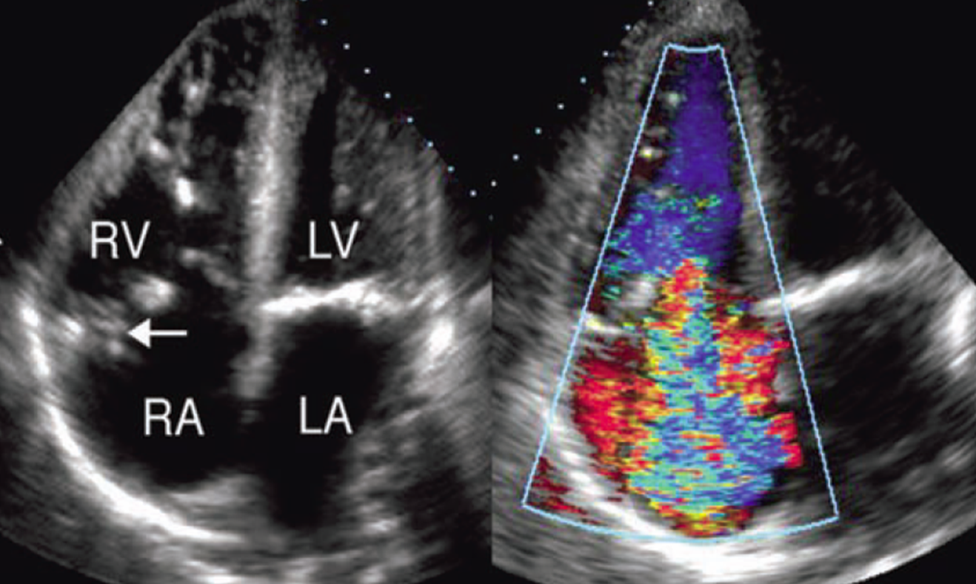

what is seen here?

tricuspid valve vegetation w/ severe regurg

color flow doppler is used to assess what in IE vegetations?

hemodynamic effect